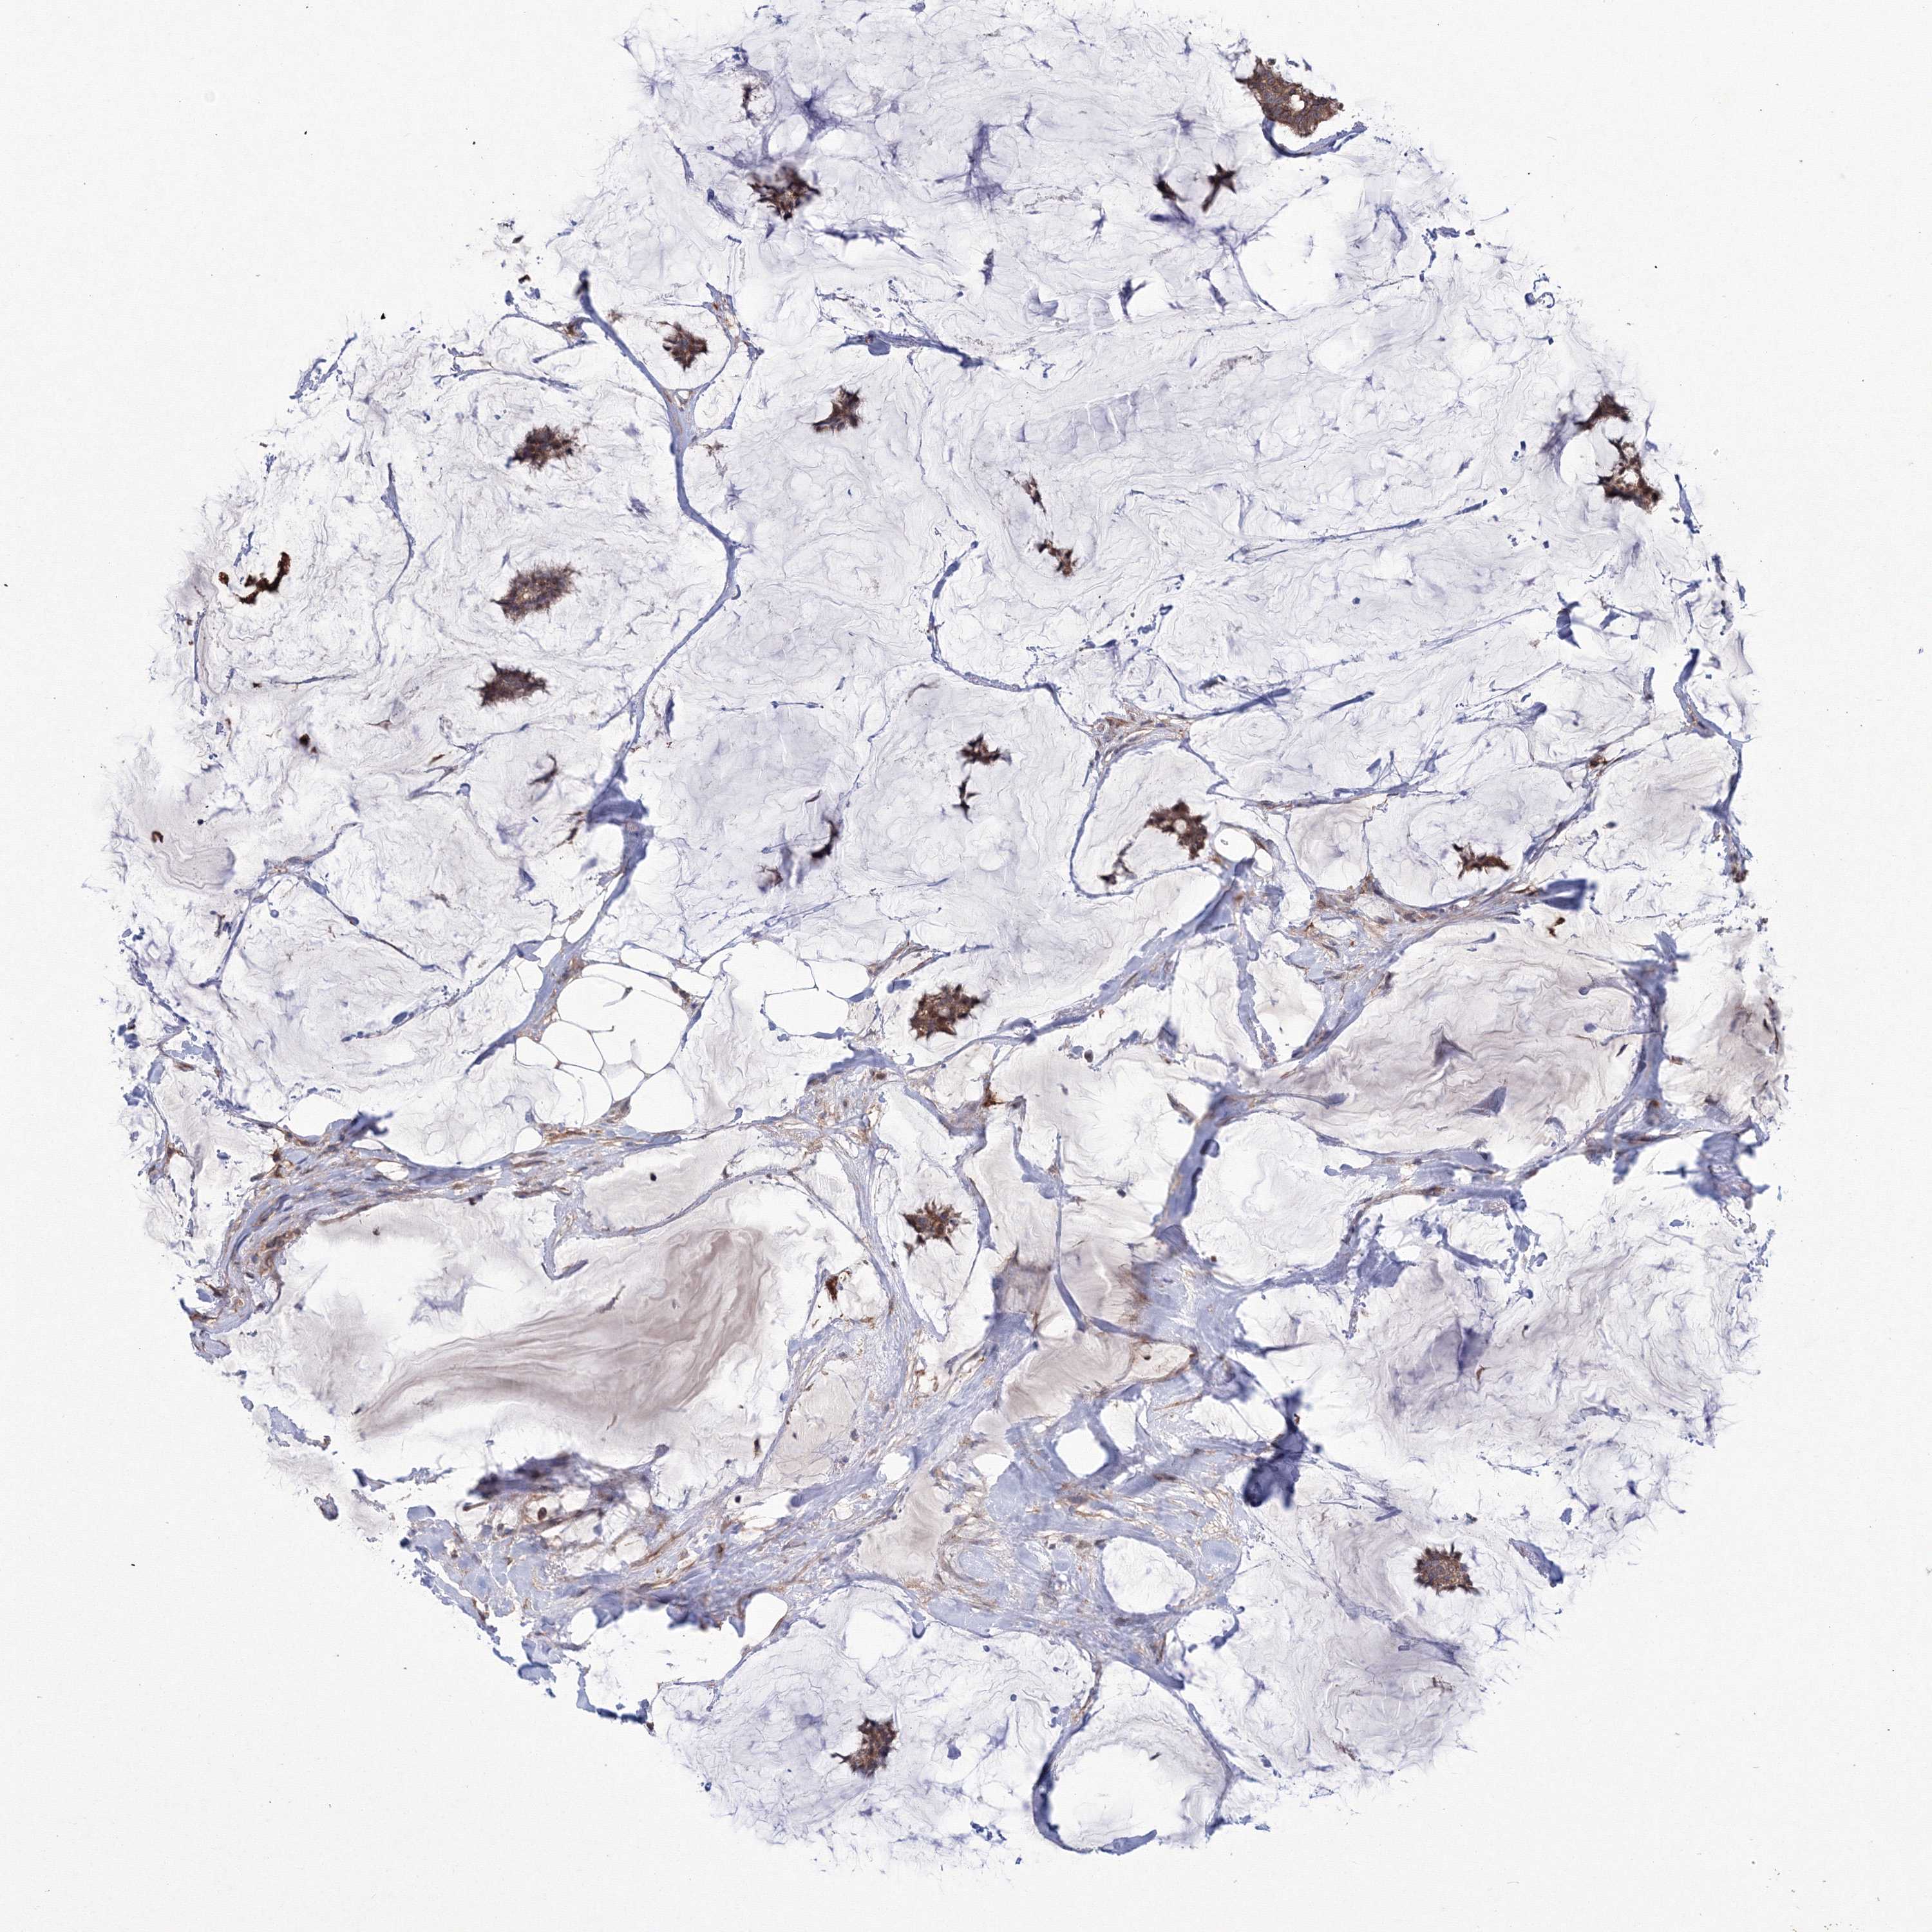

BRCA TCGA BRCA VALIDATION PROTEIN EXPRESSION

ANTIBODIES

AND

VALIDATION